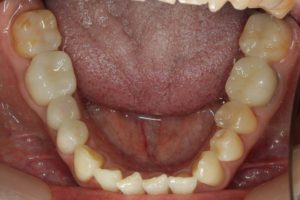

銀歯が多かったのですべて昔の銀歯の下もちりょうしながらセラミックにかえることができてとても満足しています。やっぱり白い歯よいですね。

治療お疲れ様でした。たくさん銀歯が入っていたのですが、最後には真っ白になりましたね。銀歯をやり直す材料にはセラミックとプラスティックがあるのですが、基本的にできるだけプラスティックで治すようにしています。この患者さんも、可能な限りプラスティックで治し、どうしても無理なところだけセラミックにしました。そのため歯を削る量が少ないことに加え、費用もかなり抑えることができます。たくさん治しましたが、全部セラミックで治さなければならないとなっていたら、もっともっと時間も費用もかかっていたかもしれません。当院では、初診時に治療方針や期間や費用などを1時間ほどかけて詳しく説明していますので、患者さんには治療内容について十分納得していただいていると考えています。「親身になって治療してくれる」とおっしゃっていただいたことは、そういったところを評価して頂いたのではいかと思っております。